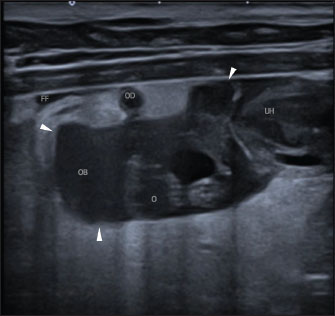

A Canon Aplio i600 ultrasound machine with convex (9-10.8 MHz) and linear (12-18 MHz) probes was used. The conscious patient was positioned in both the lateral and dorsal recumbencies. Moderate distension of both uterine horns (up to 17 mm in diameter) with immobile hyperechoic intraluminal content and irregular walls with multiple mural ovoid anechoic lesions were noted (Fig. 2). Cranial to the ovarian end of the right uterine horn and surrounding the right ovary, a 25-mm, well-defined, irregular lesion filled with mildly echogenic fluid was observed, which was compatible with a fluid-filled ovarian bursa. The adjacent peritoneum was moderately hyperechoic with a mild amount of free echogenic fluid (Fig. 3). A scant amount of free anechoic fluid was also present next to the uterine horns. A slightly tortuous tubular structure (up to 4 mm in diameter) with no color Doppler signal was identified running longitudinally adjacent to the ovary up to the uterine horn’s ovarian end, which was interpreted as the oviduct (Figs. 3 and 4). Moreover, both ovaries showed several rounded structures that were compatible with the corpora lutea. Vascularization near the lesion preserved the color Doppler signal.

Fig. 4. Abdominal ultrasonographic transversal examination in left lateral recumbency using a lineal high-frequency probe in B-mode. Lateral is to the left of the image. Note the right ovarian bursa (“OB”; the arrowheads mark the limits of the ovarian bursa), and parts of the thin, tortuous, tubular structure, compatible with the oviduct (“OD”; the highest one in the image is near the ovarian bursa, and the lowest one is next to the uterine horn’s ovarian end).